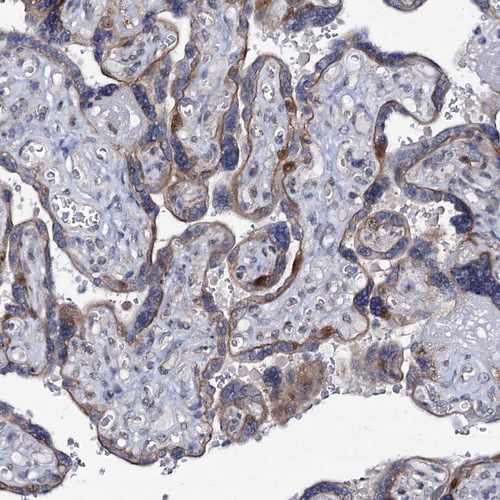

Immunohistochemical staining of human placenta shows moderate nuclear positivity in trophoblastic cells.